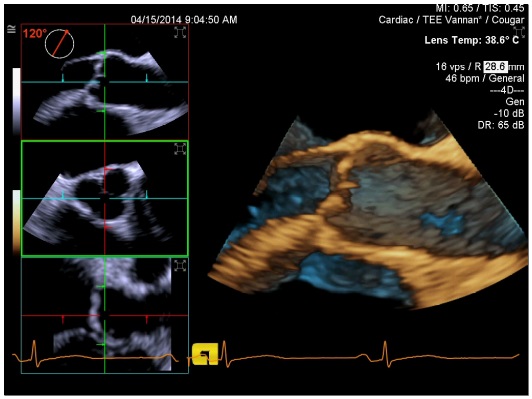

TEE 3D